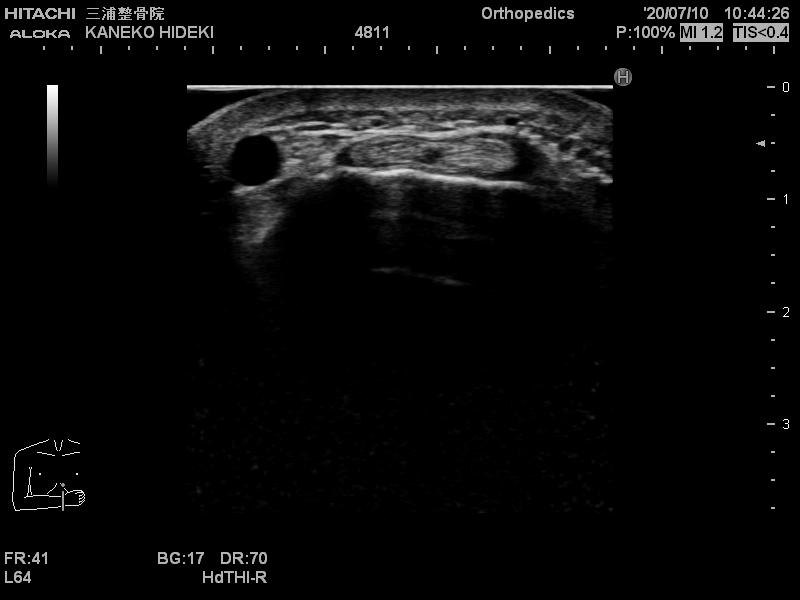

エコーではこのように映ります。

↓ドケルバン病↓

この正常とドケルバン病の画像を見比べると、患側の腱の周辺に炎症による水が溜まっている事が判ります。

本来なら腱が正常な画像とと比べて腫れているはずですが、今回の症例では両側のドケルバン病だった為、左右で差を比較することができませんでした。